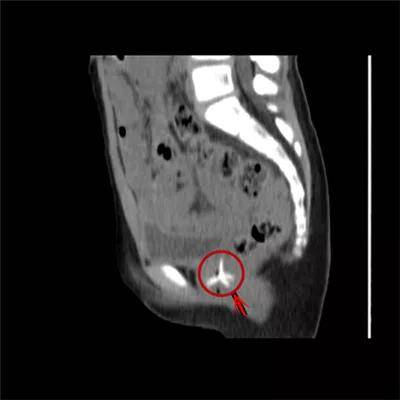

还有些异物的位置令人匪夷所思

7岁·阴道异物

塑料玩具

家长发现*裤内**上分泌物增多,结果是阴道里一年前塞进个塑料玩具。